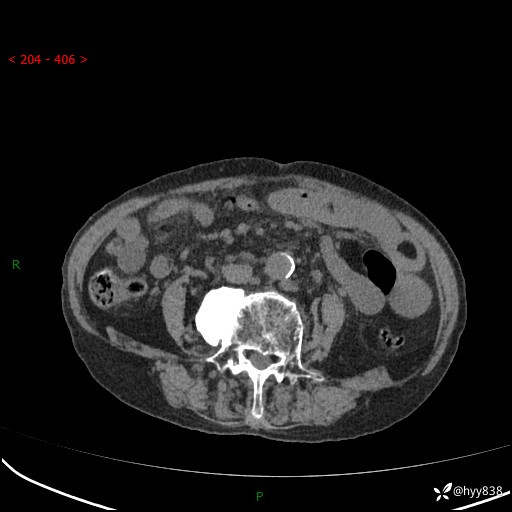

全腹部CT平扫